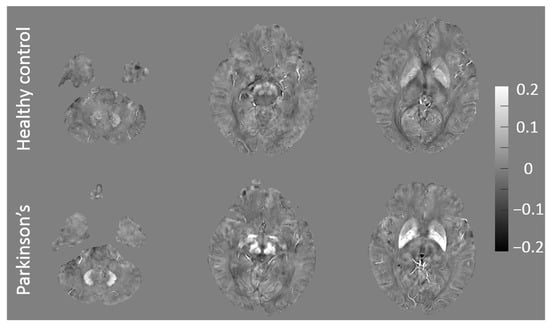

3.3. Classification Results for High and Low NMSS Score Groups

| ROI d | Mean QSM Value ± SD, ppm | F-score | |

|---|---|---|---|

| High NMSS (n = 12) | Low NMSS (n = 12) | ||

| GP e | 0.136 ± 0.029 | 0.149 ± 0.037 | 17.772 |

| RN f | 0.106 ± 0.028 | 0.099 ± 0.035 | 10.544 |

| DN g | 0.102 ± 0.033 | 0.100 ± 0.031 | 10.426 |

| SNr h | 0.129 ± 0.043 | 0.133 ± 0.045 | 9.070 |

| SNc i | 0.127 ± 0.045 | 0.134 ± 0.042 | 9.063 |

| CN j | 0.074 ± 0.027 | 0.067 ± 0.023 | 7.846 |

| PUT k | 0.111 ± 0.042 | 0.107 ± 0.056 | 5.005 |